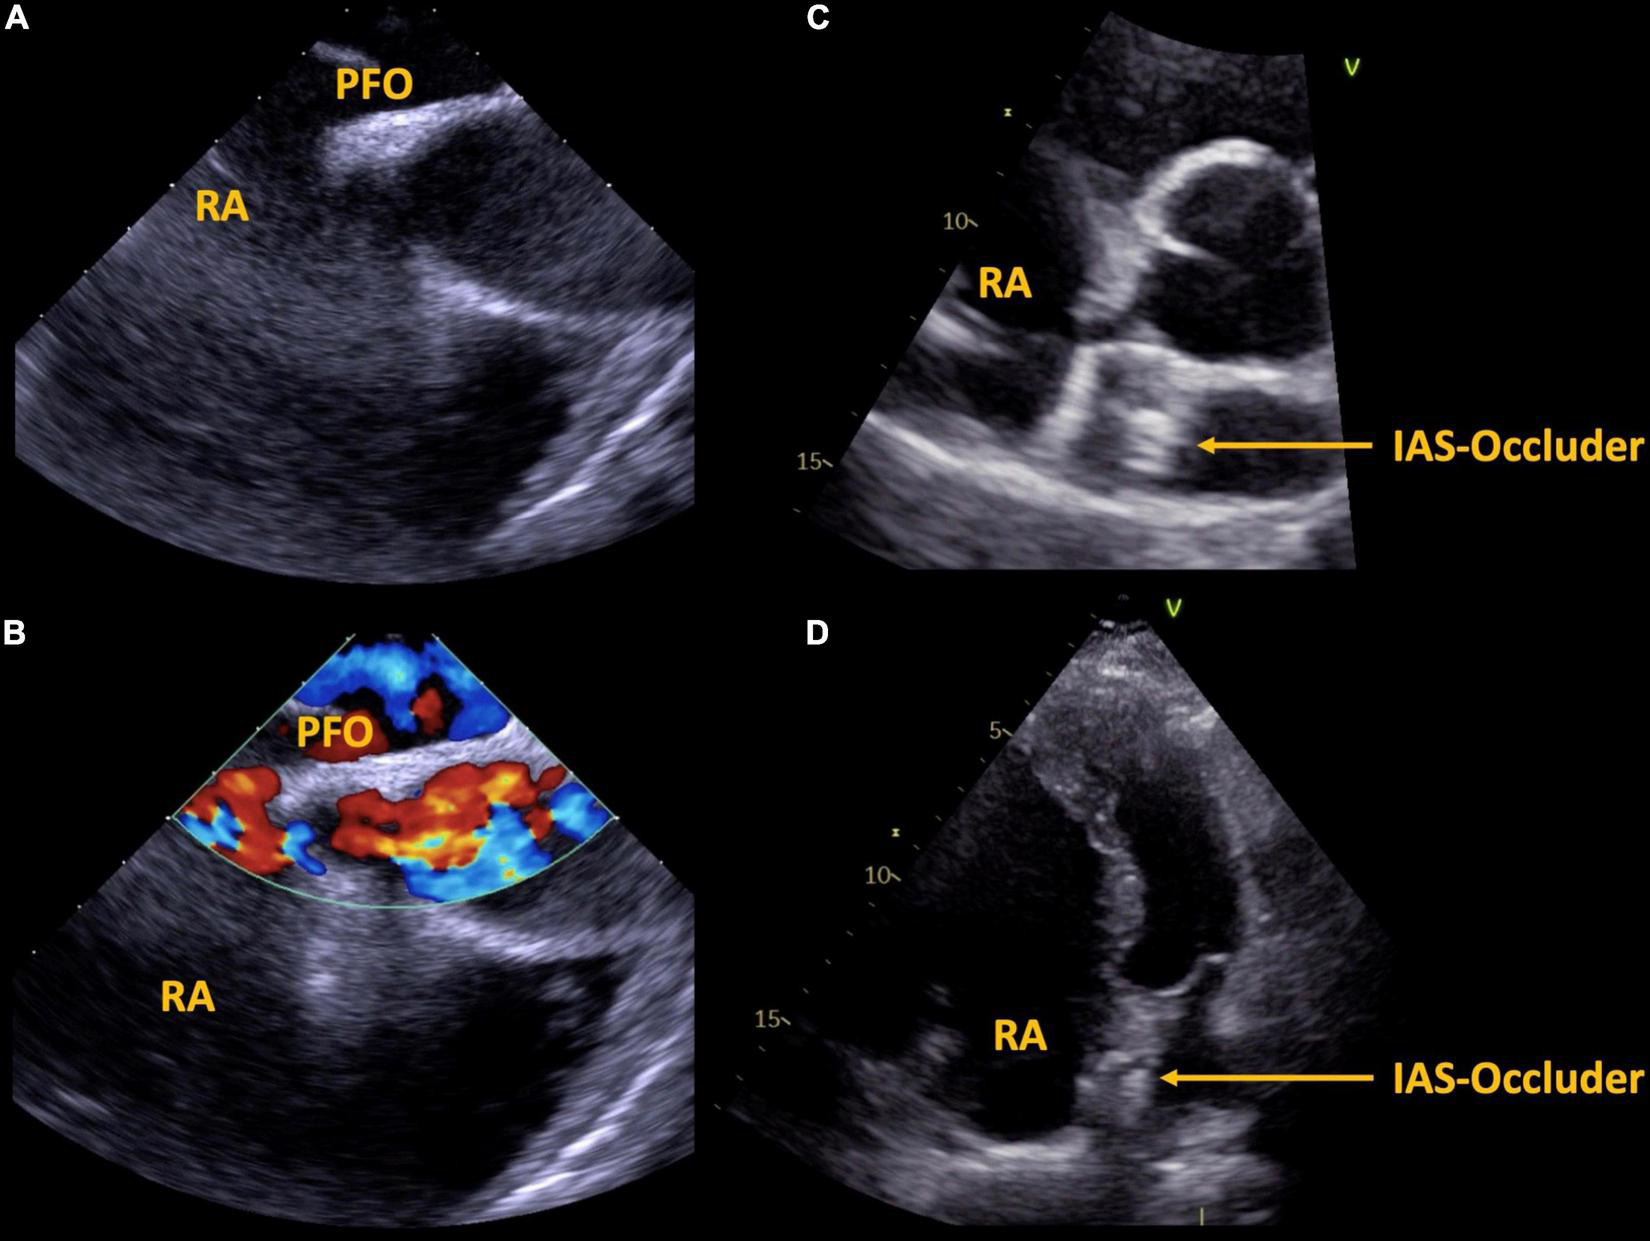

FIGURE 3

Case 2, 57 year-old patient with Ebstein’s anomaly. A large PFO is shown via transesophageal echocardiography without (A) and with (B) color Doppler imaging. Interventional septal occluder implantation was performed, the result is shown in panels (C,D). PFO, patent foramen ovale, IAS, inter atrial septum, RA, right atrium.